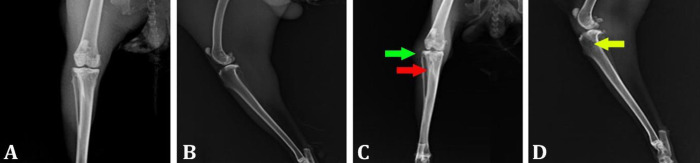

Osteomyelitis is caused by the local spread of an infected source adjacent to the infection following trauma, bone surgery or joint replacement. The present study aimed to evaluate the effect of vancomycin (Van)/polycaprolactone (PCL) nanocomposite in comparison with curcumin (Cur)/PCL on the healing of experimental osteomyelitis in tibia in rabbits. After induction of osteomyelitis forty adult male New Zealand white rabbits were randomly divided into four groups. Control group: The animals were considered as controls and no scaffolds were used. In PCL/Van group, the created bone defects were filled with the combination of PCL and Van. In PCL/Cur, the created bone defects were filled with the combination of PCL and Cur. Polycaprolactone/Cur/Van group: The created bone defects were filled with the combination of PCL, Cur and Van. Bone samples were taken for histopathological evaluation on the 30th and 60th days. For radiological evaluations of the osteomyelitis, radiographs were prepared at time intervals zero (day of surgery), 15, 30, 45, and 60 days after surgery. In order to evaluate hematology, blood was taken on days 0 (day of surgery), 15, 30, 45, and 60. The results of the present study showed that Cur nanocomposite significantly improved the healing process of the rabbit tibia experimental osteomyelitis model compared to the control group. Also, the PCL/Cur/Van group showed the best healing results. In conclusion, PCL/Cur/Van nanocomposite scaffold showed positive effects on the healing process.